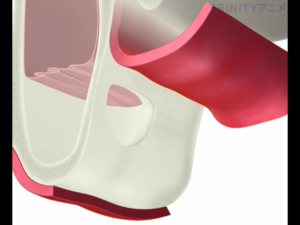

歯茎を切開し、副鼻腔につながる骨を一部削除します。

副鼻腔内の粘膜を破らないように慎重に上方に持ち上げていきます。

それによってできた副鼻腔内の空洞に人工骨を填入します。

骨を盛り上げた部分にインプラントを埋入します。

インプラントの上にドーム状に広がっているのがサイナスリフトを行い填入された人工骨です。

予定通りの場所に、予定通りの方法でインプラント手術を終えることができました。